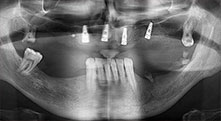

остатъчно съзъбие

40-годишен пациент с много лошо остатъчно съзъбие пожела възстановяване, базирано на импланти. Тъй като е пушач, противопоказен е синус лифт на горна челюст с фиксирана протеза. Планирано е шинирано протезиране върху четири съседни предни импланти.

Импланти

Четирите импланти са поставени на място, както е планирано. Дисталните молари на горна челюст все още могат да се използват за фиксиране на протезата, която е сложена един месец след имплантиране.